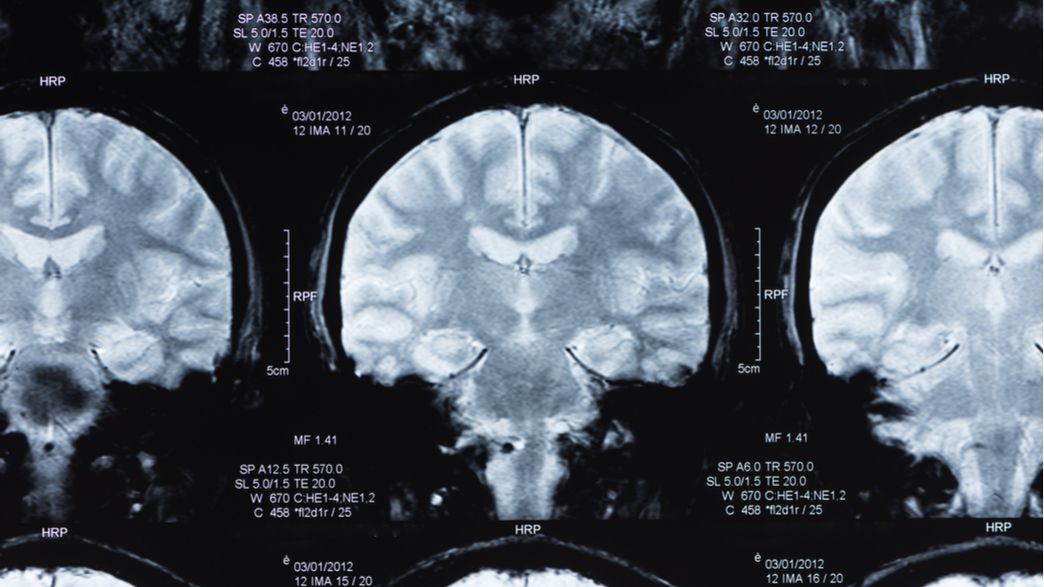

Dementia caused by Parkinson's disease Alzheimer’s disease Causes Alzheimer S Humming Frontotemporal dementia usually causes changes in behaviour or language. A doctor can check on these symptoms and do tests to know if a person has alzheimer ’s or. In the early stages of dementia, a person’s symptoms. the fact is that dementia can also affects one’s mobility, eyesight, language skills, behavior and the sensitivity to sounds. a person. Alzheimer S Humming.